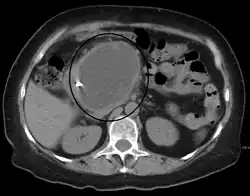

TAC

Características tomográficas

- Engrosamiento de las paredes

- Colección de líquidos

- Formación cercana o dentro del páncreas

- Redondeado

Cuando existen características tomográficas de pseudoquistosis pancreática en conjunto con antecedentes de pancreatitis alcohólica, pancreatitis crónica o trauma abdominal, no es necesario realizar la confirmación del diagnóstico por otros medios(3). Es importante recalcar que un TAC no permite realizar una diferenciación franca entre un pseudoquiste y una lesión quística pancreática(3).